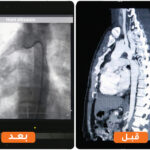

With skilled hands and unwavering hearts, the team successfully performed the dilation using a covered stent (Begraft) through the cardiac catheterization lab. By the grace of God, the procedure was a resounding success!

Immediately after the procedure, Hani’s blood pressure returned to normal, and the pulse in his lower limbs was restored, allowing him to move without pain or fatigue. After close monitoring, Hani was discharged from the hospital in excellent condition, ready to start a new chapter of his life, free from suffering.